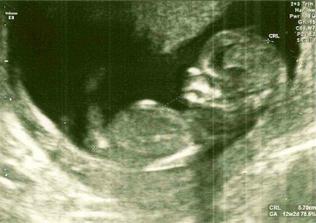

Čakáme miminko!